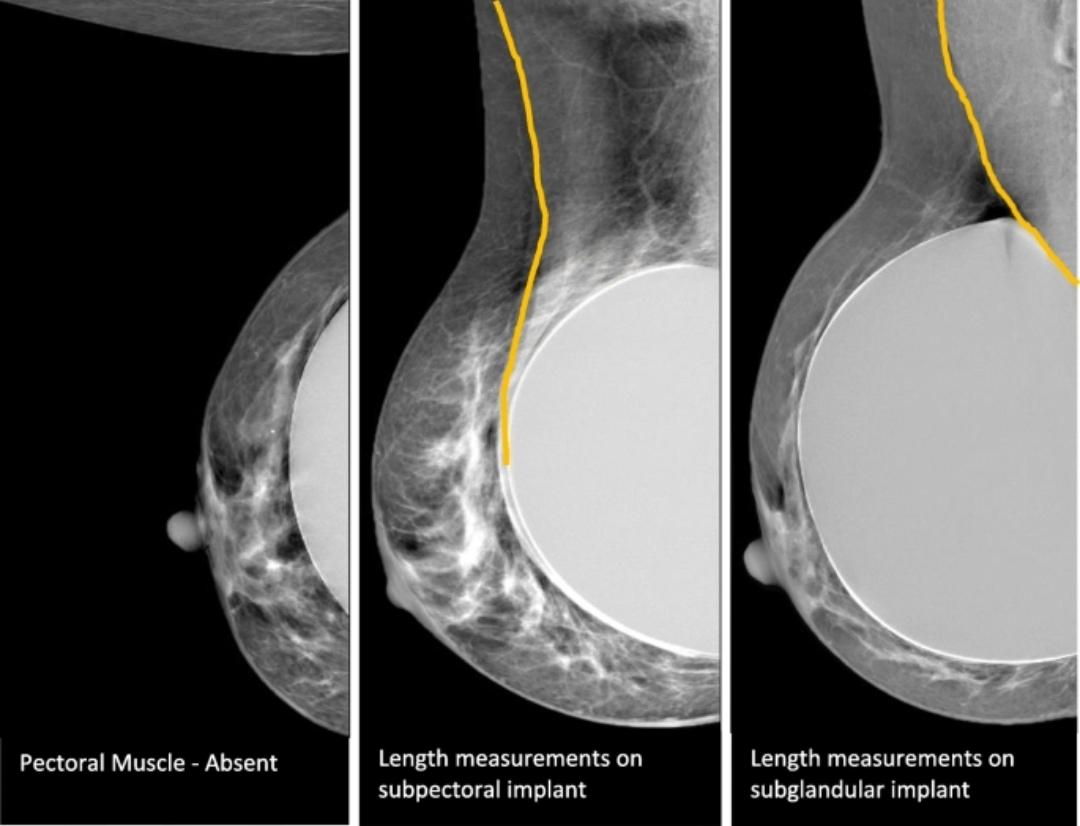

가슴 보형물 삽입 후에도 유방촬영술은 원칙적으로 시행 가능합니다. 다만 일반인과 동일한 방식이 아니라 보형물을 최대한 뒤로 밀고 유방 조직만 당겨 촬영하는 특수 기법(Eklund view)을 사용합니다. 이 경우 진단 정확도는 유지되면서 보형물에 가해지는 압력은 줄일 수 있습니다.

보형물 파열 위험은 이론적으로 존재하지만 매우 드뭅니다. 특히 수술 후 3년 경과, 증상이 없고 최신 장비를 사용하는 의료기관이라면 실제 위험도는 낮은 편입니다. 다만 실리콘 보형물의 미세 파열 여부를 확인하는 데에는 유방촬영술보다 MRI가 더 민감합니다.

정리하면, 유방암 검진 목적이라면 유방촬영술을 피할 이유는 없고, 보형물 상태 평가가 주목적이거나 파열이 걱정된다면 MRI가 더 적절합니다. 현실적으로는 유방초음파를 기본으로 하고, 필요 시 유방촬영술 또는 MRI를 병행하는 전략을 많이 사용합니다.